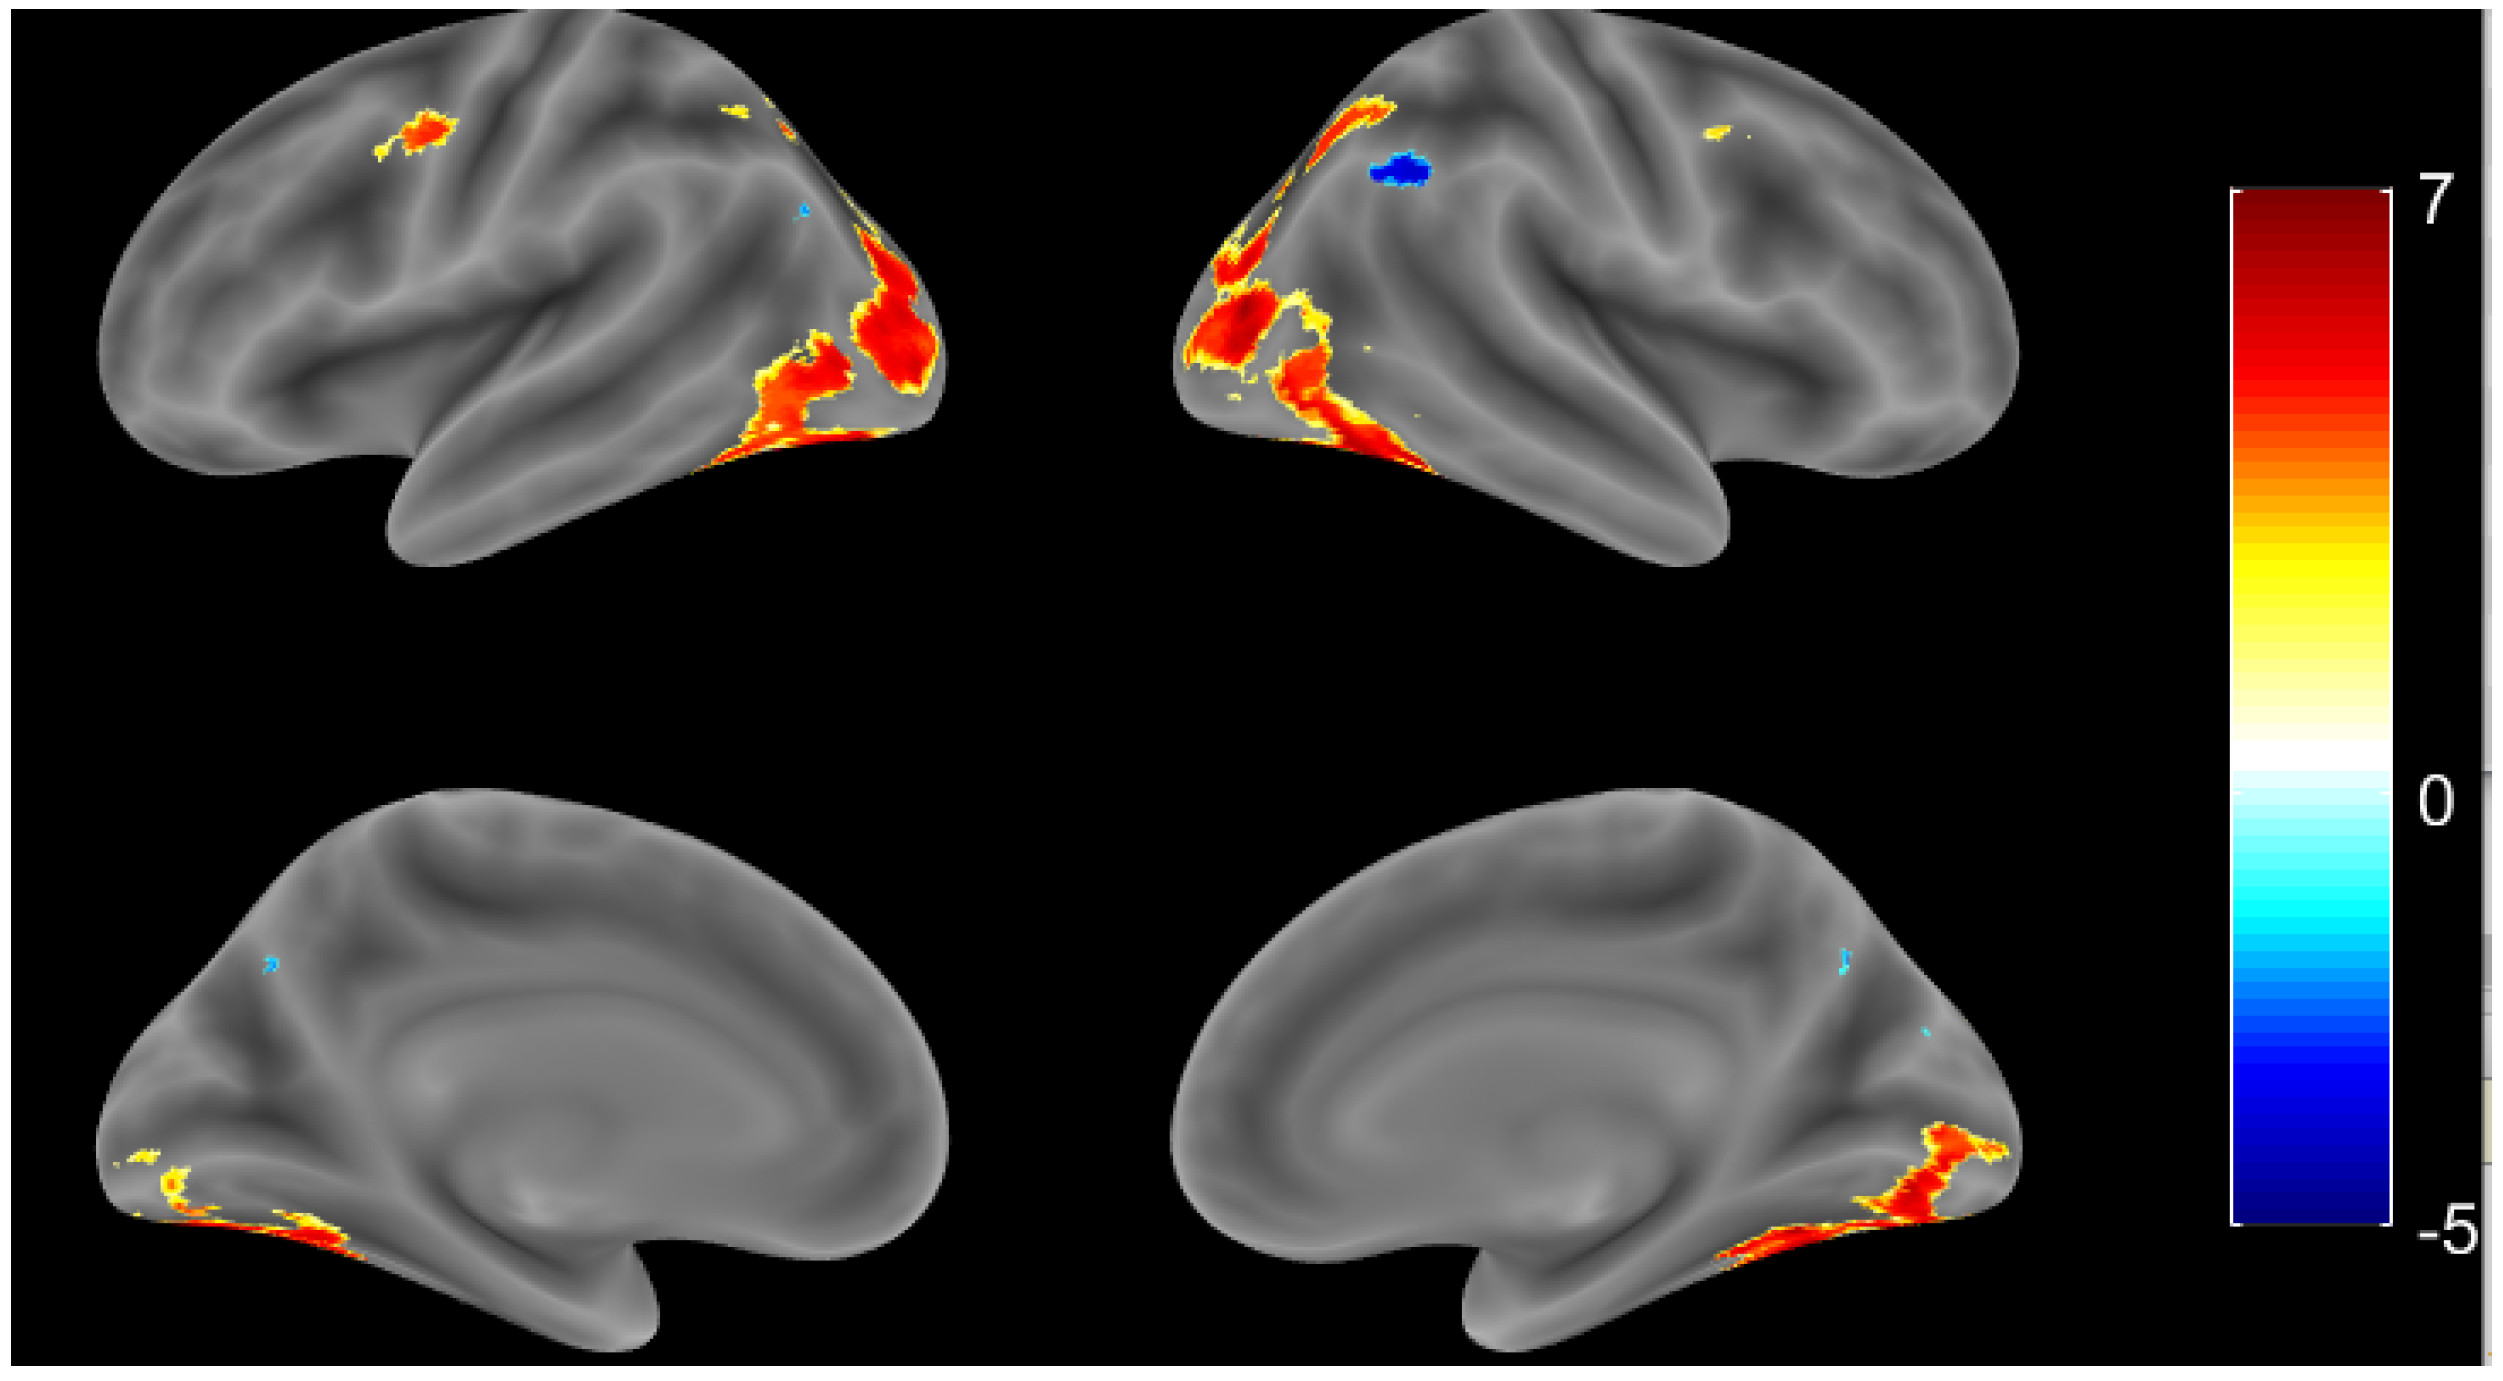

3.1. Healthy Controls

3.1.1. Whole Brain Analysis

3.2. Alzheimers Disease

3.2.1. Whole Brain Analysis

3.3. Group Comparison

3.3.1. Whole Brain Analysis

| Region Label | Extent | T Value | MNI Coordinate | ||

|---|---|---|---|---|---|

| x | y | z | |||

| R fusiform gyrus | 11,475 | 12.7884 | 42 | −60 | −14 |

| L fusiform gyrus | 11,475 | 10.5606 | −20 | −90 | −2 |

| L cerebellum (III) | 106 | 5.8934 | −4 | −48 | −14 |

| L IFG (p. triangularis) | 1018 | 5.7927 | −38 | 32 | 10 |

| L precentral gyrus | 1018 | 4.955 | −46 | 0 | 48 |

| L posterior-medial frontal | 264 | 5.7539 | 0 | 8 | 62 |

| L IFG (p. orbitalis) | 210 | 5.591 | −52 | 20 | −2 |

| R insula lobe | 316 | 5.479 | 36 | 20 | 4 |

| R temporal pole | 316 | 4.8344 | 58 | 10 | 2 |

| R precentral gyrus | 278 | 5.2847 | 52 | 8 | 44 |

| L fusiform gyrus | 5421 | 7.300 | −32 | −76 | −12 |

| R lingual gyrus | 5421 | 7.288 | 22 | −84 | −6 |

| R fusiform gyrus | 5421 | 7.237 | 36 | −56 | −12 |

| L putamen | 24 | 5.508 | −26 | −22 | 4 |

| L precentral gyrus | 114 | 5.110 | −52 | 2 | 46 |

| R middle frontal gyrus | 13 | 4.520 | 42 | 6 | 46 |

| R thalamus | 9 | 4.497 | 28 | −28 | 6 |

| L superior parietal lobule | 24 | 4.480 | −22 | −68 | 50 |

| L middle occipital gyrus | 40 | 4.468 | −24 | −60 | 42 |

| L IFG (p. triangularis) | 6 | 4.284 | −52 | ||